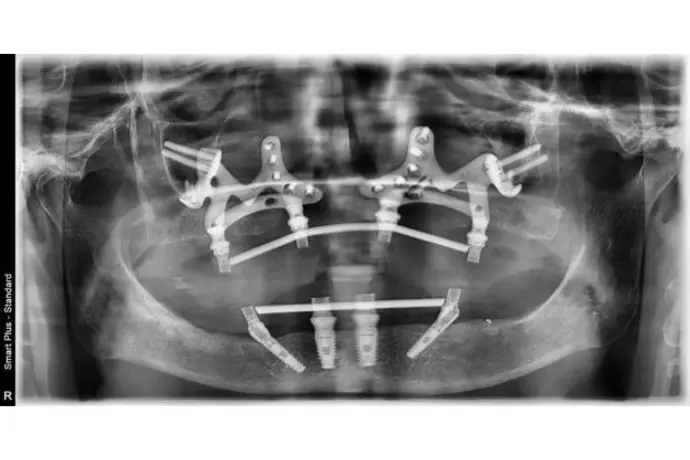

Référentiel Full Arch Club : All-on-4, All-on-X, palatal approach, trans-sinus, pterygoïdes, subpériostés personnalisés. Moins invasif, plus sûr.

• Chirurgie et mise en charge immédiate avec une approche sans greffes osseuse  et prédictible.

Opération chirurgicale en direct réalisée par le Dr Bernardo Nunes de Sousa